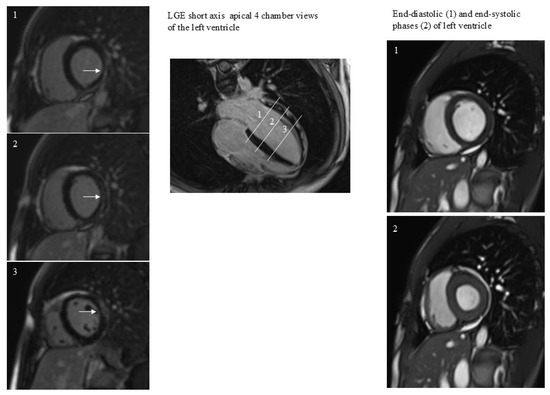

Non-Ischemic Pattern of LGE After COVID-19 Correlates More with Severity of Acute Illness than with Long-Term Myocardial Dysfunction

by Alessandro Pingitore, Filippo Figini, Laura Pederzoli, Patrizia Landi, Luca Bastiani, Claudio Marabotti and Filippo Leonardo

J. Clin. Med. 2025, 14(21), 7477; https://doi.org/10.3390/jcm14217477 - 22 Oct 2025

Background/Objectives: Myocarditis can occur in patients with coronavirus disease 2019 (COVID-19) as part of the systemic involvement of this infectious syndrome. The persistence of this non-ischemic late gadolinium enhancement (LGE) pattern can be considered an indicator of ongoing myocardial involvement or a [...] Read more.

Background/Objectives: Myocarditis can occur in patients with coronavirus disease 2019 (COVID-19) as part of the systemic involvement of this infectious syndrome. The persistence of this non-ischemic late gadolinium enhancement (LGE) pattern can be considered an indicator of ongoing myocardial involvement or a sequela of myocarditis. We aimed to assess the effects of LGE on cardiac function and morphology in patients with COVID-19 admitted in intensive care unit for acute respiratory distress syndrome. Methods: Fifty patients (age 59 ± 11, female n = 15) were enrolled. Results: The prevalence of LGE was 33.3%. LGE was present in the lateral wall in all patients except for one, with LGE positivity at the interventricular septum. In general, patients with and without LGE had similar CMR variables values. In one case, LGE was associated with regional wall motion abnormality. The factor associated with LGE was the duration of hospitalization (7.97 ± 3.8 and 12.5 ± 6.7 days in patients without and with LGE, p = 0.007). Conclusions: LGE non-ischemic pattern was not associated with left ventricular dilatation or dysfunction or remodeling in patients with severe clinical manifestation of COVID-19. LGE is mainly present in patients with more prolonged duration of hospitalization. LGE may represent a residual scar with limited prognostic impact that larger multicenter studies could confirm. Full article